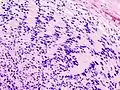

Периваскулярные псевдорозетки

Периваскулярные псевдорозетки состоят из спицевидных структур с конусообразными клеточными отростками, расходящимися вокруг стенки расположенного в центре сосуда. Приставка «псевдо» показывает различие этих розеток от розеток Гомера Райта и Флекснера-Винтерстайнера, потому что центральная структура розетки фактически не формируется самой опухолью, а вместо этого представляет собой нативную, неопухолевую ткань. Кроме того, некоторые ранние исследователи спорили об природе центрального просвета, выбирали приставку «псевдо», чтобы указать, что центр не является истинным просветом, а содержит гистологические структуры.[2]

Периваскулярные псевдорозетки встречаются в большинстве эпендимом независимо от степени злокачественности или варианта. Они значительно более важны для диагностики эпендимомы, чем истинные эпендимальные розетки. Но к сожалению, периваскулярные псевдорозетки менее специфичны — они также встречаются в медуллобластомах, PNET, центральных нейроцитомах и, реже, в глиобластомах, а также в редких детских опухолях, мономорфных пиломиксоидных астроцитомах.[2]

Периваскулярные псевдорозетки в эпиндимоме

Эпендимальные псевдорозетки вокруг пролиферирующего эндотелия при анапластической эпендимоме